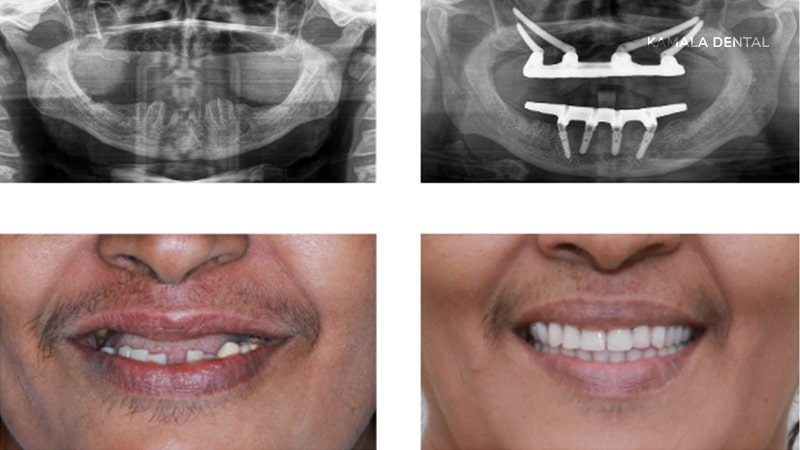

Quad Zygoma Technique

When the bone in the front and back parts of the upper jaw is less than 2 mm in width, two implants can be anchored into each zygomatic bone. This creates a strong foundation and offers a reliable fixed solution in cases of severe bone loss.